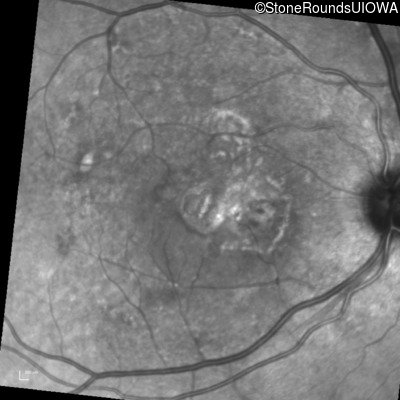

Fundus Photography - Left - 20/20

Exemplar